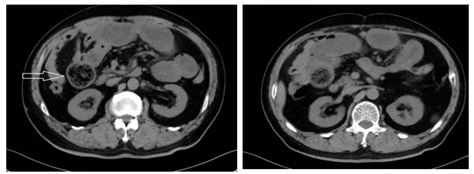

CT表现为边界清晰的椭圆形低密度肿块,斑驳的肿块外观是由于肿块间隙内留有气泡所致。

患者男,68岁,既往胃大部切除术,进食山楂后出现上腹部疼痛,呈持续性绞痛阵发性加重,伴恶心、呕吐,呕吐物为胃内容物。CT图箭头指示结石位于上段空肠,以上胃肠道明显扩张。